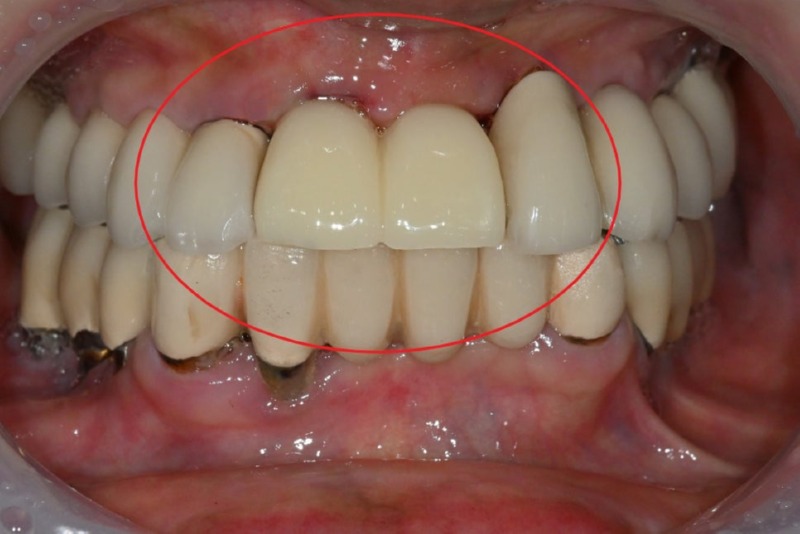

치료 전

수술 3주 후

수술 후 단 3주만에,

앞니 임플란트 보철물까지 장착하였고,

환자분은 어떠한 불편함도 없다고 하셨습니다.